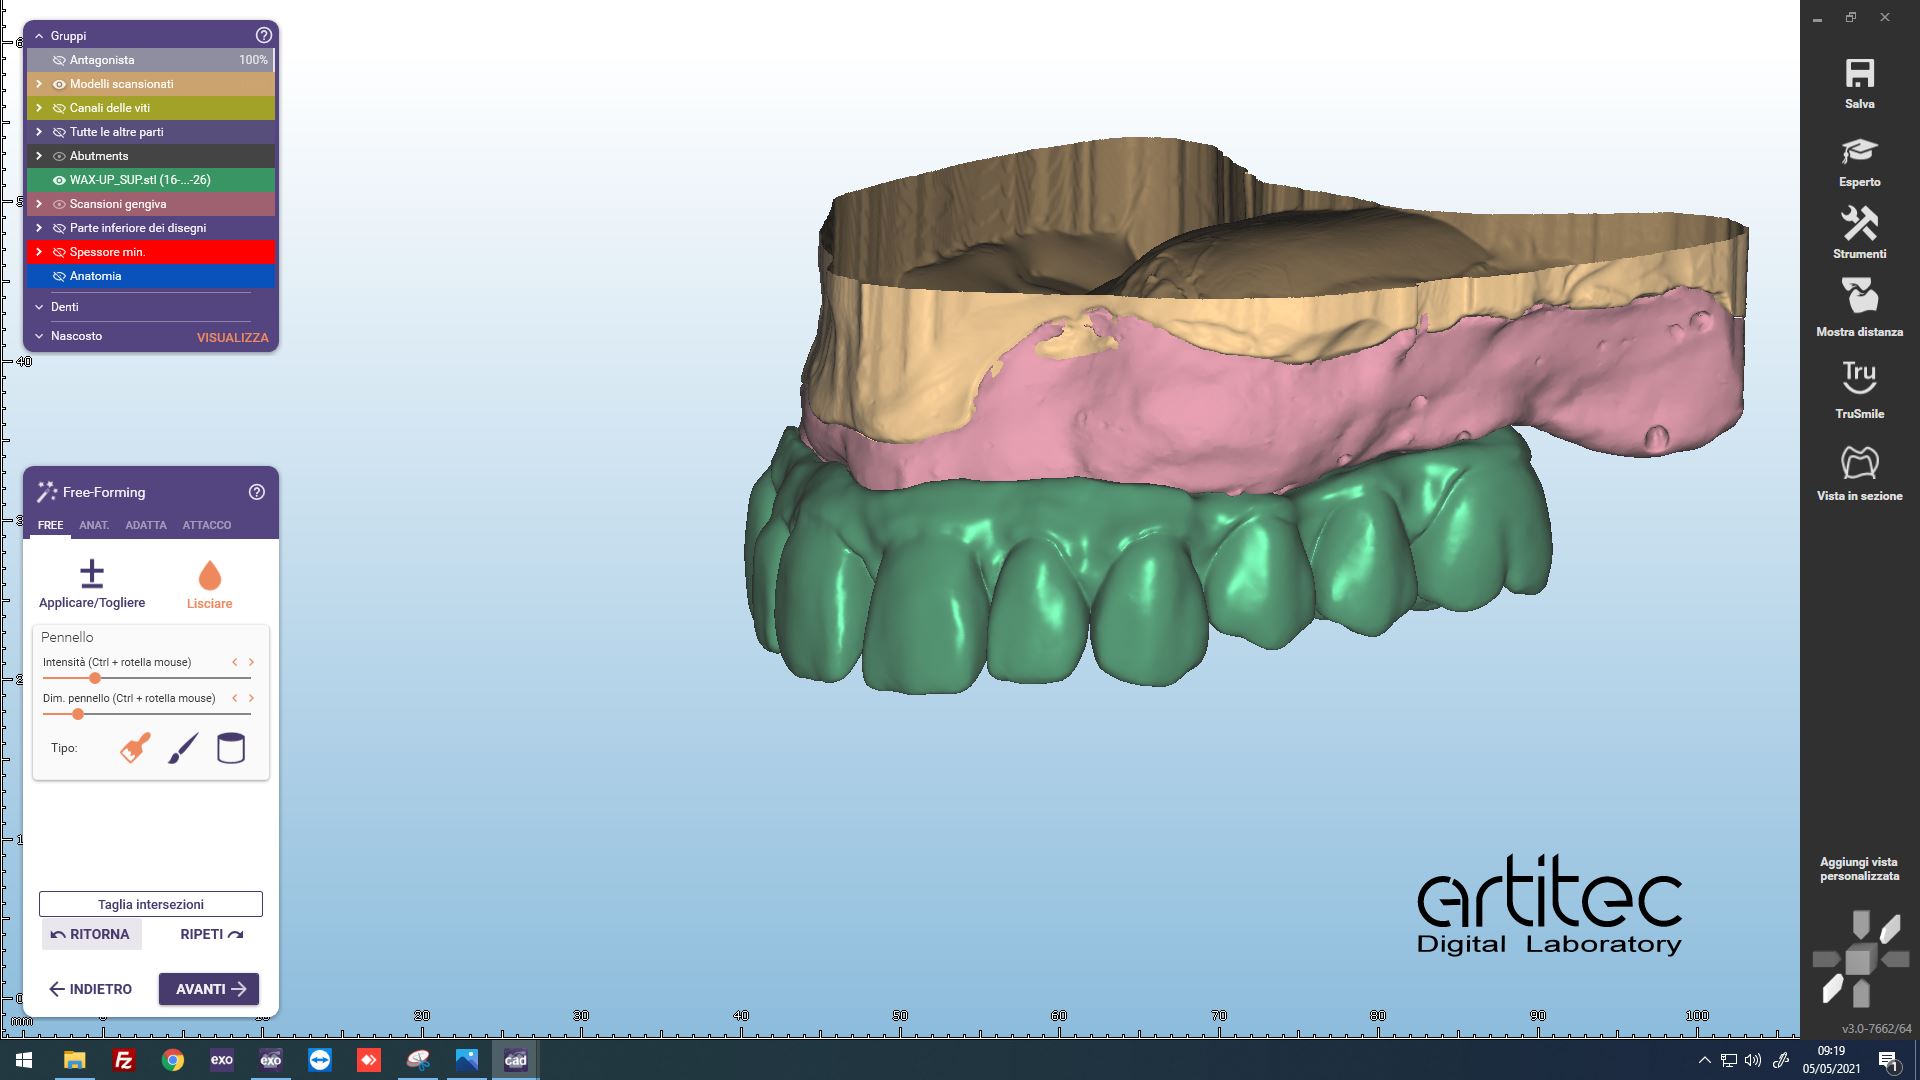

Fig. 5 Posizionamento anatomie dalle informazioni della scansione del provvisorio

Fig. 6 Posizionamento anatomie CAD/CAM